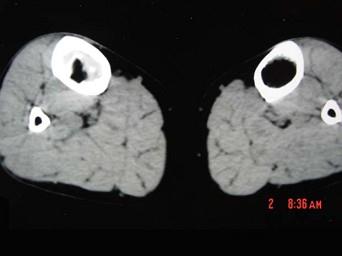

问题 患者 女,19岁,3个月前自觉右胫骨部疼痛,有轻度肿胀,请结合所提供的图像,选择最佳选項 ( )

选项 A、纤维性骨皮质缺损 B、骨样骨瘤 C、造釉细胞瘤 D、骨纤维结构不良 E、骨囊肿

答案 D